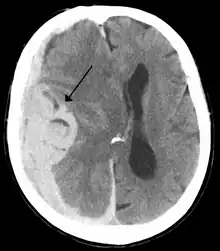

Midline shift

Midline shift is a shift of the brain past its center line.[1] The sign may be evident on neuroimaging such as CT scanning.[1] The sign is considered ominous because it is commonly associated with a distortion of the brain stem that can cause serious dysfunction evidenced by abnormal posturing and failure of the pupils to constrict in response to light.[1] Midline shift is often associated with high intracranial pressure (ICP), which can be deadly.[1] In fact, midline shift is a measure of ICP; presence of the former is an indication of the latter.[2] Presence of midline shift is an indication for neurosurgeons to take measures to monitor and control ICP.[1] Immediate surgery may be indicated when there is a midline shift of over 5 mm.[3][4] The sign can be caused by conditions including traumatic brain injury,[1] stroke, hematoma, or birth deformity that leads to a raised intracranial pressure.